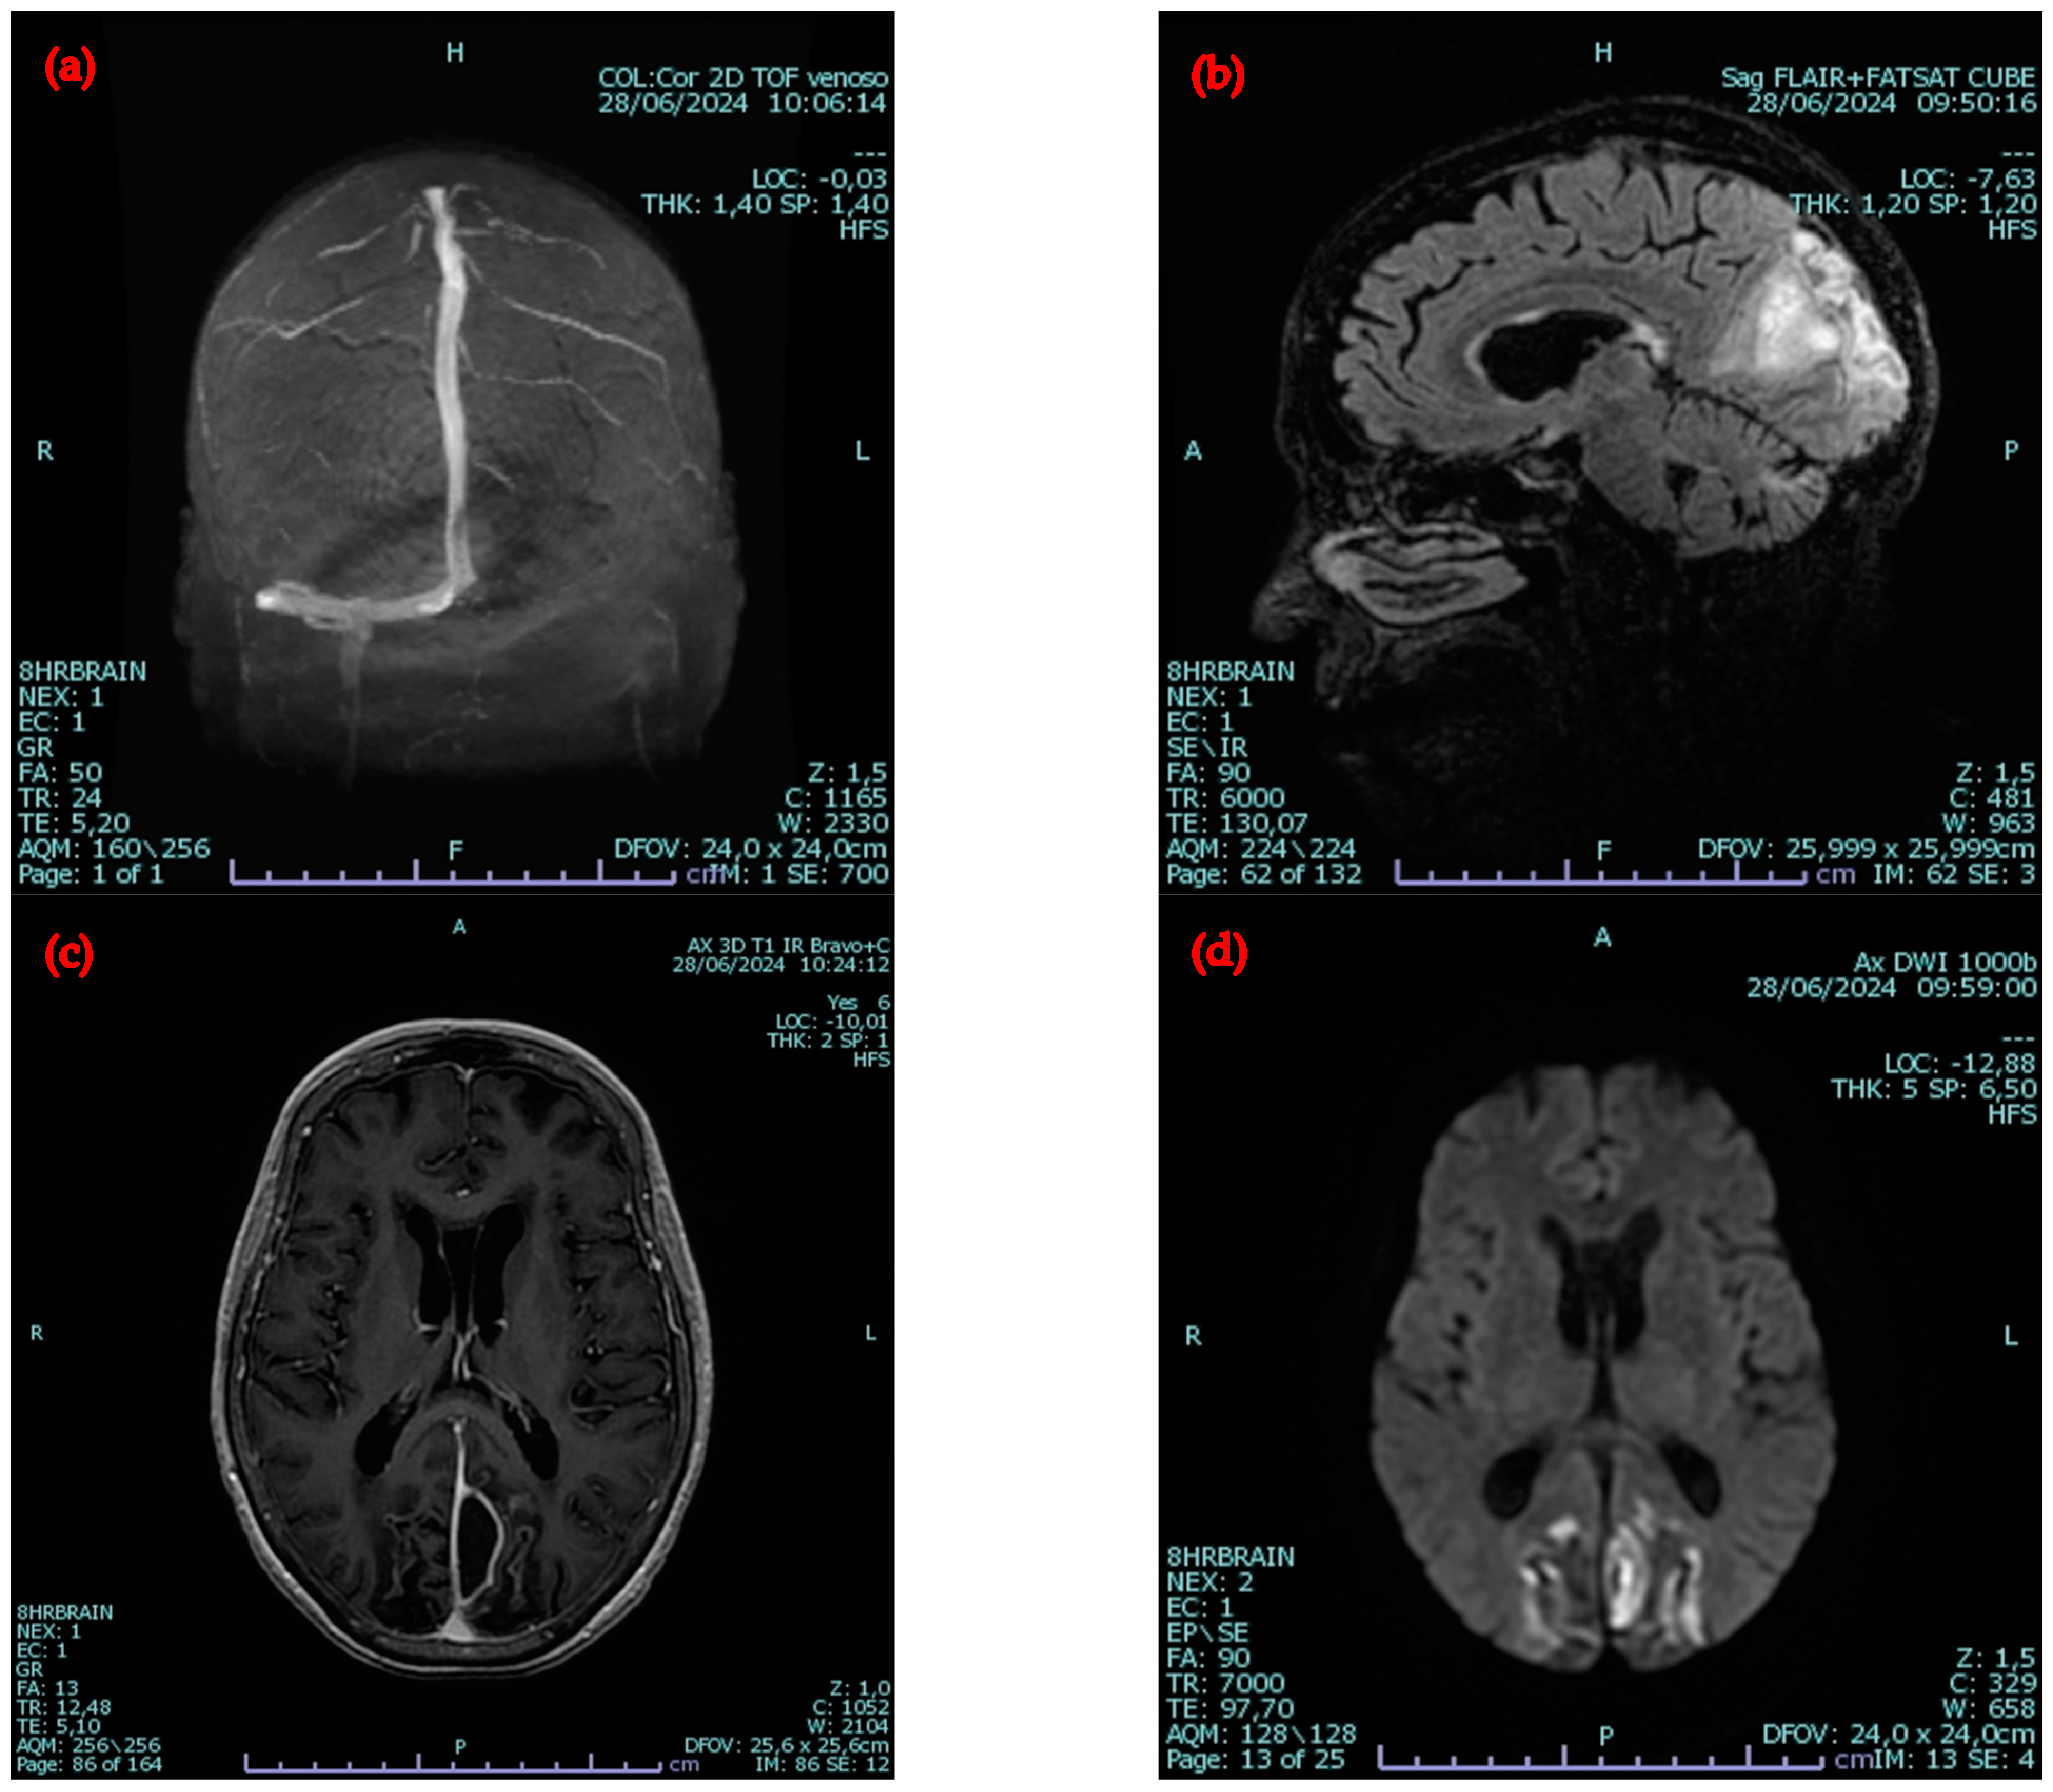

2.2. Second Admission to the Same Hospital

2.3. Admission to the Infectious Diseases Unit of Our University Hospital

4.4. Venous Thromboses and Other Complications